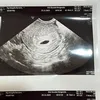

Kabar bahagia datang dari keluarga Ayu Ting Ting. Syifa umumkan sedang mengandung anak kedua lewat akun Instagram pribadi sang ibunda. Semua anggota keluarga, tak terkecuali Ayu Ting Ting pasti sangat senang karena akan bertambah lagi baby menggemaskan. Simak potret lengkapnya berikut ini!

Rasa bahagia tak dapat disembunyikan dari Syifa dan keluarga. Adik Ayu Ting Ting ini sedang mengandung anak kedua, jangan skip foto-fotonya saat sedang cek ke dokter kandungan.